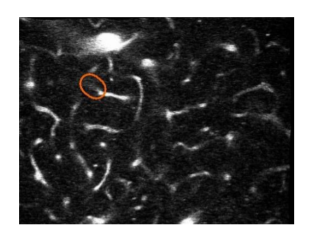

- After extracting the frames and manual filtering of the images, a dataset of 78675 images in total was created. If we observe the dataset in a scrupulous manner, we find out that the difference between the images as a whole is quite inconsequential. The difference between both the classes viz. blood flowing and stalled in the cranial vessel can be determined only by the region outlined in these images. So, unless and until we consider just the outlined region, the difference in both the classes seems irrelevant. Hence, extraction of the outlined region in a particular image becomes extremely important.

5. The above images where then classified using four distinct architectures viz. Resnet50, Resnet101, Resnet152 and AlexNet. The logic that is used in the classification is that in case when blood is actually flowing through the vessel a luminescent spot is picked up by the algorithm whereas in case when the blood is not flowing or stalled a black spot can be observed. So when we are looking at images of a non Alzheimer individual the frequency of these bright luminescent spots would be higher as compared to the black spots and vice versa for an Alzheimer infected person. Whichever algorithm is able to best pick up this difference will give us the highest accuracy